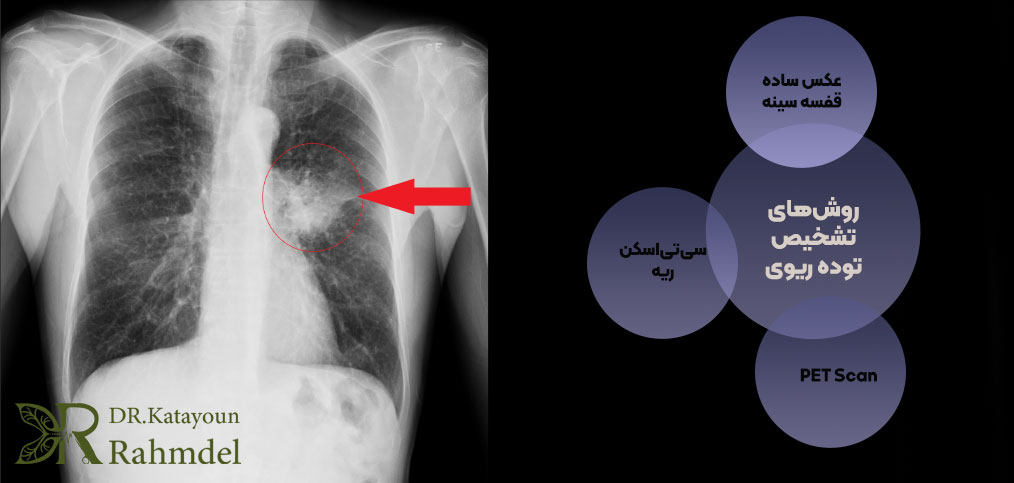

بهترین روشهای تشخیص تودههای ریوی

۱. عکس ساده قفسه سینه (X-ray Chest) | قدم اول تشخیص

عکس ساده قفسه سینه معمولاً اولین روشی است که برای کشف توده ریوی استفاده میشود. بسیاری از بیماران به دلیل سرفههای مداوم، درد قفسه سینه یا حتی در یک چکاپ روتین این تصویربرداری را انجام میدهند و در همان مرحله وجود یک ضایعه در ریه مشخص میشود. این روش سریع، ارزان و در دسترس است و حتی میتواند برای پیگیری رشد توده در طول زمان مورد استفاده قرار گیرد.

با این حال، محدودیتهایی نیز دارد؛ از جمله اینکه جزئیات دقیق توده را نشان نمیدهد و قادر به تعیین ماهیت آن نیست. به همین دلیل، در صورت مشاهده هرگونه ضایعه در عکس ساده، قدم بعدی و ضروری، انجام سیتیاسکن قفسه سینه برای بررسی دقیقتر است.

۲. سیتیاسکن ریه (CT Scan) | دقیقترین روش تصویربرداری اولیه

3. PET Scan روش تعیین میزان فعالیت سلولی | (تشخیص بدخیمی)